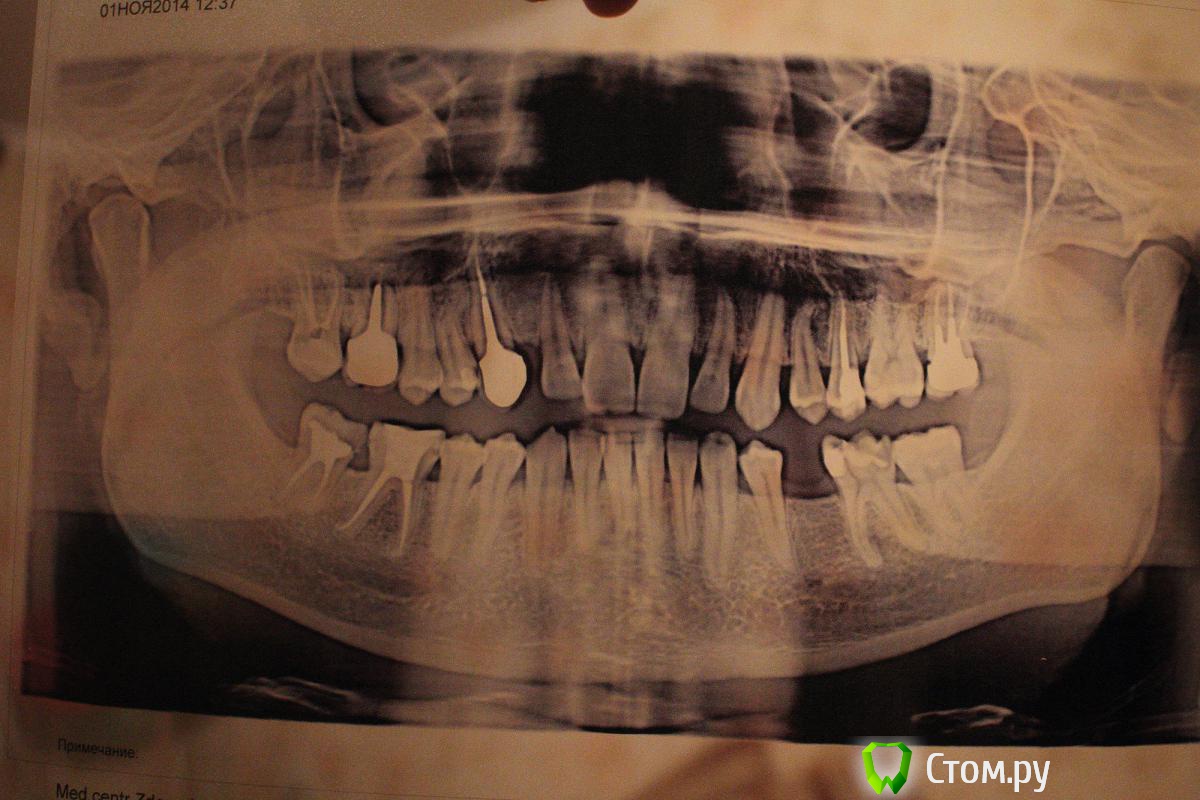

Алексей1983 Опубликовано 6 ноября, 2014 Поделиться Опубликовано 6 ноября, 2014 Здравствуйте!Хотел бы узнать мнение врачей форума по поводу моего случая.У меня пару недель назад появилась белая шишечка на десне. В районе шестого верхнего зуба справа. Ходил к стоматологу, которая сказала, что у меня свищ и нужно делать рентген. По результатам рентгена дала заключение, что кисты нет. А все, что рекомендуется делать, это уколы линкомицина в десну. Сделал в другом месте панорамный снимок и проконсультировался у другого специалиста. Получил следующее мнение: кисты пока нет, но она может скоро образоваться. На зубе стоит коронка. Ни терапевтическое, ни хирургическое лечение невозможно. Случай неоперабельный (причины:1) очень близко расположена гайморова пазуха, 2) наличие металлической коронки)). Поэтому только удаление. Также проконсультировался в Интернете, где получил ответ, что зуб, скорее всего, придется удалять по причине того, что в нёбном корне зафиксирована огромная металлическая вкладка и при её извлечении корень наверняка треснет.Что касается моих ощущений, в общем-то, меня беспокоит только сам факт наличия свища. Ничего не болит, щека не опухала, температуры нет. К этому письму я прикрепляю панорамный снимок. Не могли бы вы посмотреть его и сказать:- Что у меня с шестым верхним зубом справа? Гранулема?- Действительно ли в моем случае не поможет никакое лечение (даже хирургическое) и зуб придется удалять? Заранее большое спасибо вам за ответы! Ссылка на комментарий

Алексей1983 Опубликовано 7 ноября, 2014 Автор Поделиться Опубликовано 7 ноября, 2014 Дополнительно к панорамному прикрепляю прицельный снимок этого зуба. Ссылка на комментарий

Бобр Опубликовано 7 ноября, 2014 Поделиться Опубликовано 7 ноября, 2014 Для начала сделать рентгенснимок с гуттаперчей в свище, чтобы доказать, что причинный зуб именно шестой. А уже потом думать как вкладку вынимать. корневые каналы в шестом зубе безусловно имеют недоделки Ссылка на комментарий

faity Опубликовано 7 ноября, 2014 Поделиться Опубликовано 7 ноября, 2014 а мне и 5-ый не нравится, плюсую к снимку с гуттой Ссылка на комментарий

Бобр Опубликовано 7 ноября, 2014 Поделиться Опубликовано 7 ноября, 2014 В том то и дело, что и в пятом какие-то намеки у верхушки, да и коронка у него не проснята. А вдруг свищ имеет пародонтальную природу Ссылка на комментарий

victor57 Опубликовано 7 ноября, 2014 Поделиться Опубликовано 7 ноября, 2014 ну а как же гранулема на мезиальном корне 6-го? гутаперча гутаперчей, а я считаю - если терапевты не берутся, и другие не берутся, то что его вытягивать? Ссылка на комментарий

Алексей1983 Опубликовано 7 ноября, 2014 Автор Поделиться Опубликовано 7 ноября, 2014 ну а как же гранулема на мезиальном корне 6-го? гутаперча гутаперчей, а я считаю - если терапевты не берутся, и другие не берутся, то что его вытягивать?Большинство врачей, с которыми я общался очно или заочно, действительно говорят о том, что зуб нужно удалять. Во-первых, из-за металлической вкладки, при извлечении которой может треснуть корень. Во-вторых, из-за близости корней к гайморовой пазухе. Есть и два врача, которые готовы попробовать полечить этот зуб. Один из них предполагает, что можно вообще не трогать вкладку. Я не готов точно процитировать его слова. Но примерно план такой (моими словами): "поскольку гранулема у одного корня, можно к ней подобраться в обход вкладки, провести какие-то процедуры, перепломбировать и воспаление исчезнет". Ссылка на комментарий

DmitrySH Опубликовано 7 ноября, 2014 Поделиться Опубликовано 7 ноября, 2014 Проблему с 6 зубом видно и без КТ. И основной вопрос в том, что останется от зуба после извлечения вкладки. Заранее, на основании снимков и КТ, это невозможно прогнозировать. Ссылка на комментарий